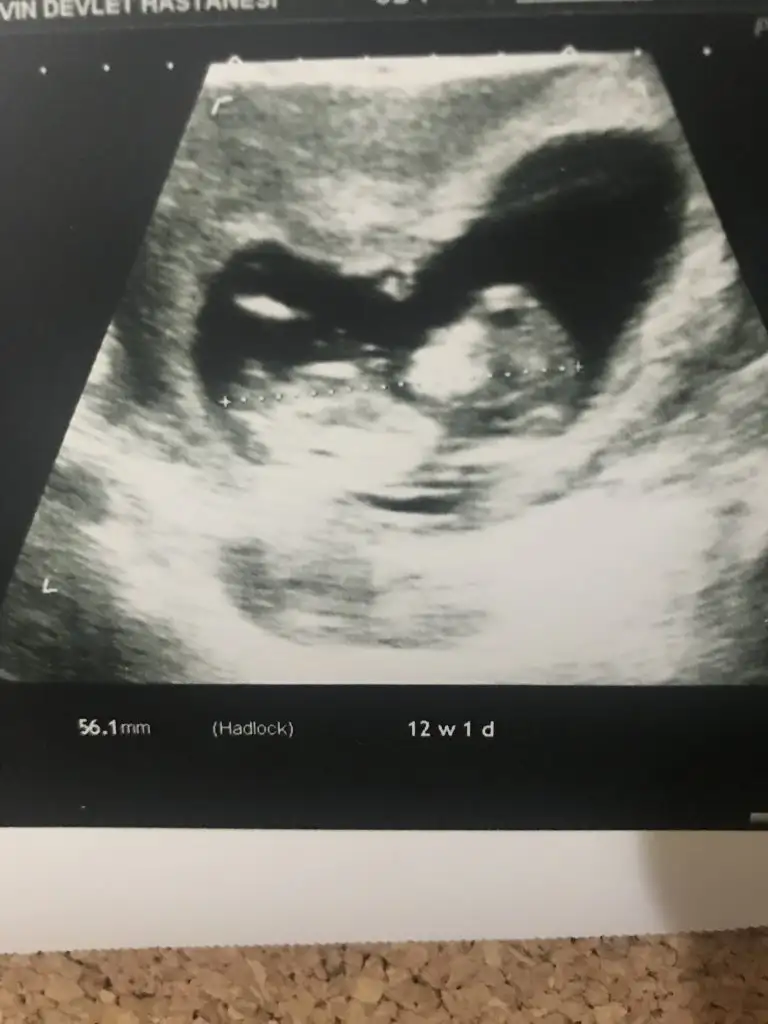

Ikra meyra bu ultrasonlara gore bebek hangi tarafda ve cinsiyet tahmini ney.

Bunlarda ayni.